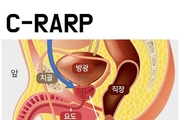

남성, ‘사정’ 자주 할수록 전립선암 위험 줄어든다